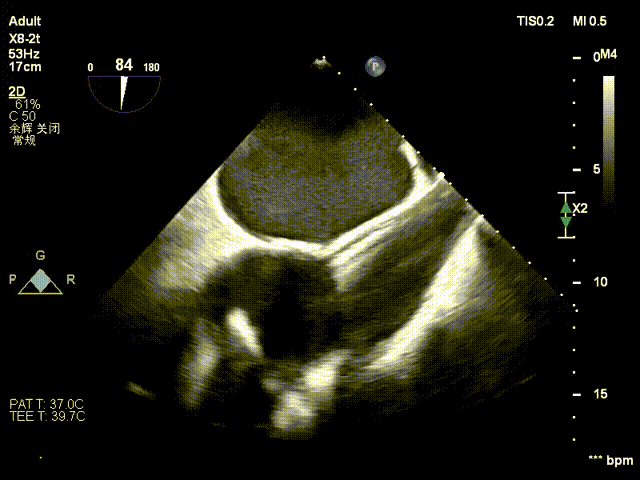

经右颈内静脉穿刺建立通路,置入18Fr鞘管,将K-Clip®输送系统送达右心房。依托三维经食管超声心动图(3D TEE)联合 DSA 双模态引导,经验精准定位瓣环,于后隔交界(P-S commissure)植入14T规格K-Clip®,前后交界(A-P commissure)植入16T规格K-Clip®,实现瓣环多点精准环缩。每枚夹子释放后,团队实时通过超声评估瓣叶对合及反流改善情况,严格遵循 “精准定位 - 锚定验证 - 安全解离” 的规范化操作流程,确认无瓣叶损伤、瓣口狭窄及心包并发症后,完成器械解离与撤出。

3. 控弯旋转输送器指向靶点,3D MPR平面攻入锁定螺丝

4. 调整Oreintation后夹持臂着陆,缓慢关闭夹持臂

5. 第二枚夹子同样操作,三维下夹子形态稳定